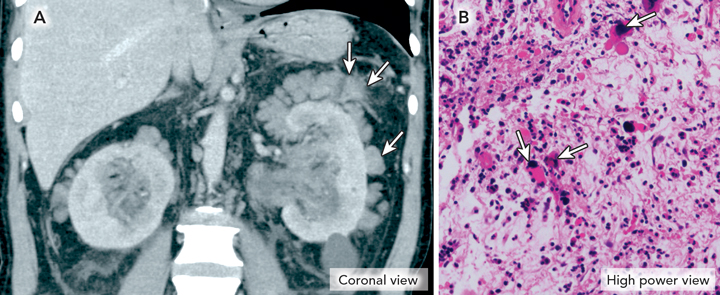

A 59-year-old man presented with persistent abdominal discomfort 12 months after splenectomy for thrombocytopenia to ameliorate progressive myelofibrosis. Physical examination revealed bilateral loin masses. Computed tomography of the abdomen identified perinephric cuffing by soft tissue nodular masses in the perinephric fat (Figure A). Core needle biopsy of the right perinephric fat revealed haematopoietic cells (Figure B).